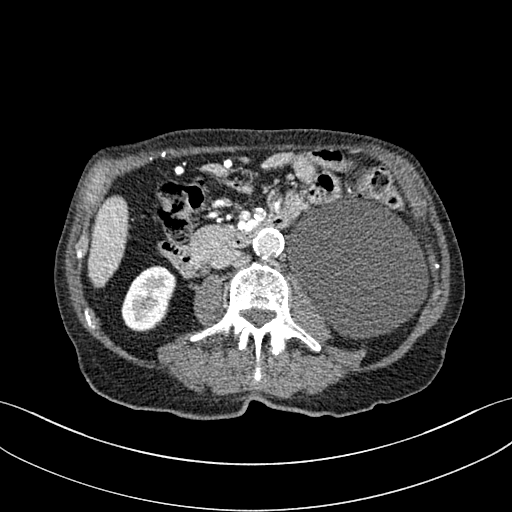

Figure 6: Result of denoising for comparison. We have shown an example of denoising performance on image taken from the 2016 NIH-AAPM-Mayo Clinic Grand Challenge dataset. The display window is [140140-140, 260] HU for better visualization of low attenuated lesion. Readers are requested to zoom in for better view.

Figure 7: Comparison of denoising performance of different network. Zoomed view of the region inside the bounding box shown in the images for Figure 6

As shown in Table 3, DIP has exhibited the worst performance among all the methods. On the other hand, the ConsensusNet yielded a better FID and TML than BM3D but a lower PSNR and SSIM than other methods. The ConsensusNet divided the original projection data of the low dose CT image into two subgroups and back-projected to create the noisy input signal. Consequently, the noisy input image is much noisier than the original LDCT image. Also, the structural loss occurred during the generation of noisy images, so as a result, the PSNR and SSIM of this method are lower than other methods. Texture matching loss (TML) is used to measure the texture difference between the reconstructed and original images. The lower value of TML indicates that the generated texture is similar to the original. In comparison, FID estimates the distance between the distribution of the generated image and real images. A lower value of FID signifies the generated images are more similar to the original image. The current deep learning era demands a denoised image with a low value of these metrics. These denoised images may be used as input for other image classification tasks or segmentation networks. In this regard, the ConsensusNet is superior to the BM3D because it uses the deep neural network’s expression power. CycleGAN is another powerful unsupervised method for image-to-image translation; it achieved better performance than the other methods. However, CycleGAN has a lot of bottlenecks, e.g., longer training time, computation power, hyper-parameter tuning, etc. All these bottlenecks make CycleGAN ill-suited for practical deployment. Meanwhile, our proposed method has achieved the highest PSNR, SSIM, FID, and VIF among all the other methods. Next, we compare the result of denoising visually in Figure 6. It can be observed that the proposed method performs significantly better than the other unsupervised methods. BM3D output produced a blurry denoised image and contained many splotchy artifacts. The same blurriness can be observed in the output of ConsensusNet, and DIP, although noise suppression is adequate, and splotchy artifact is absent. In the output of CycleGAN, we can observe the presence of residual noise, especially in the high noise regions. Next, we identified one low attenuated lesion in the sample image and marked the lesion with a red colour bounding box. The zoomed view of the region inside the bounding box is given in Figure 7. In our method’s output image, the lesion’s visibility is enhanced significantly than in other methods. Despite being an unsupervised method, the visibility of the lesion is comparable with the original NDCT image. Also, from the zoomed view, we can perceive that our method has suppressed the granular pattern without losing the original image’s texture.